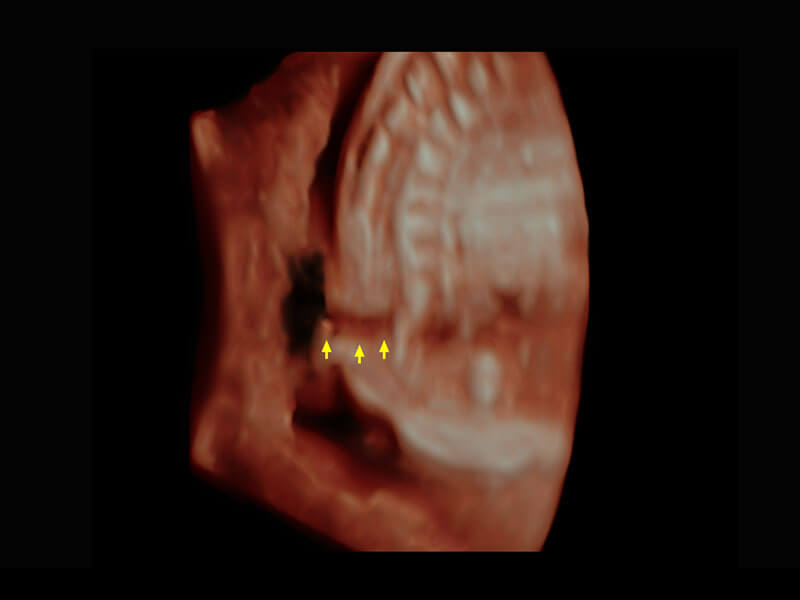

腔内三维-宫内节育器